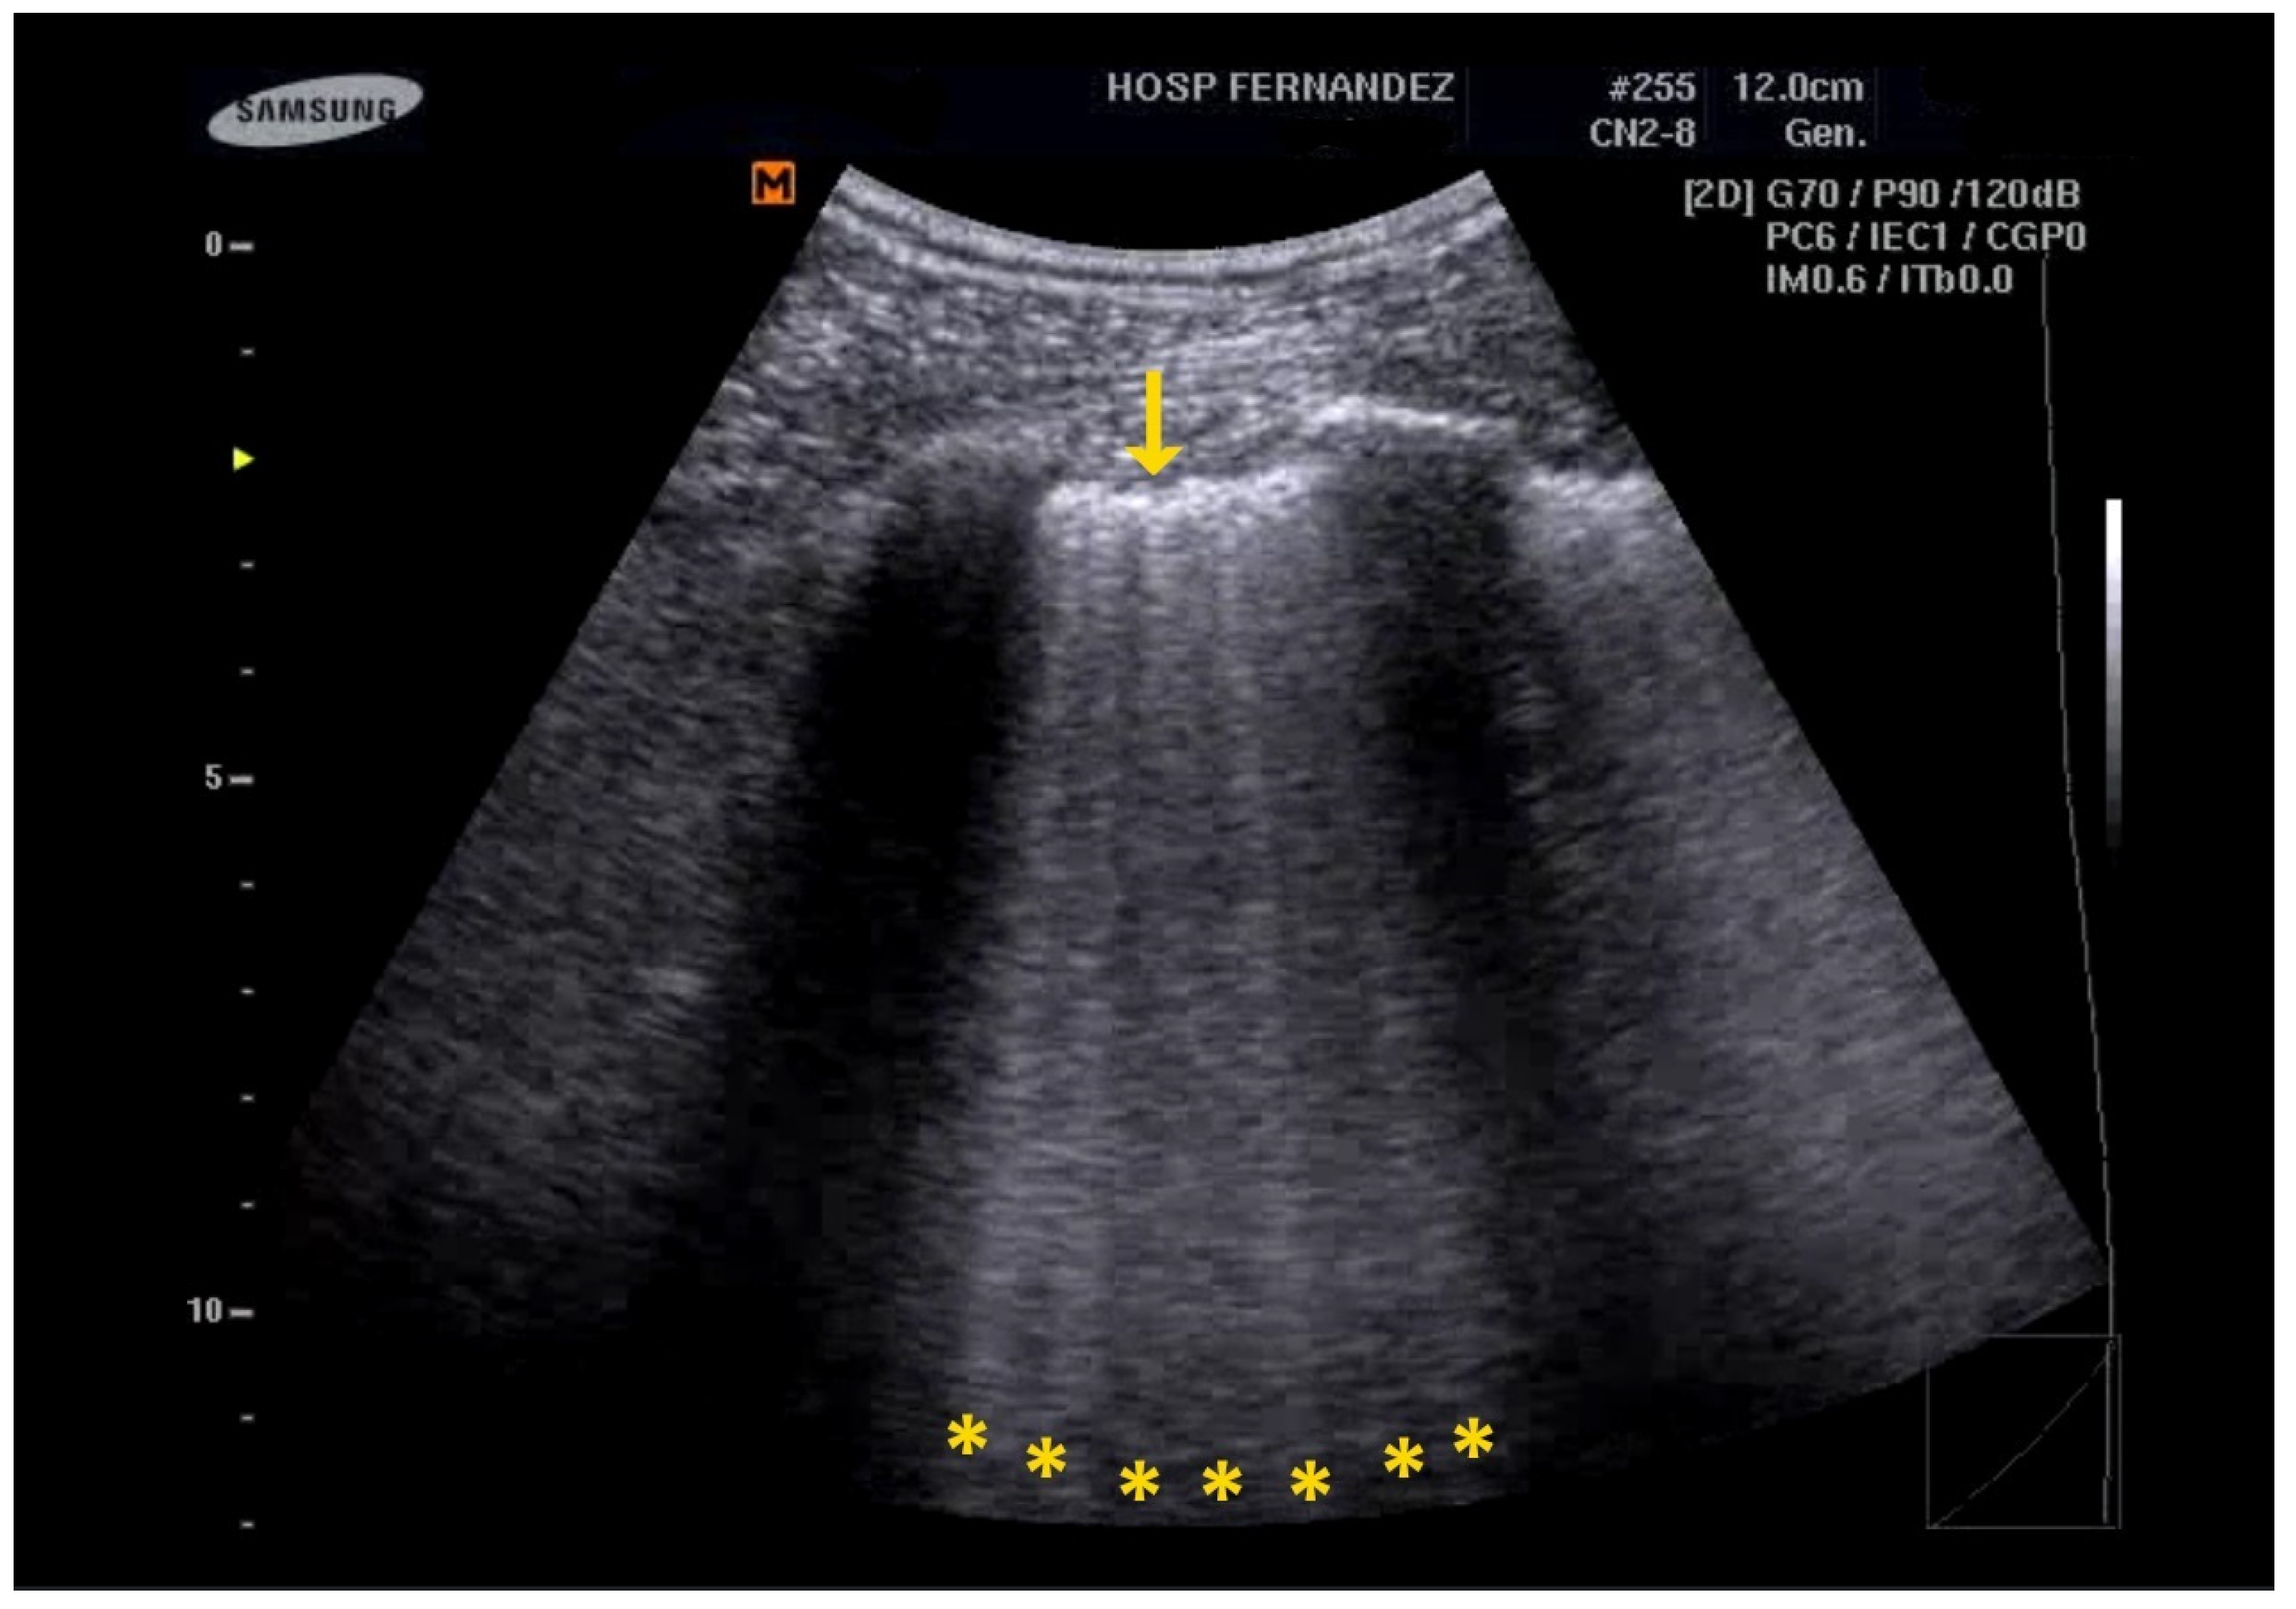

- Multiple B-Lines: These appear in a diffuse, inhomogeneous distribution and are critical for ILD diagnosis.

- Pleural Line Abnormalities: These may include thickening, irregularities, and fragmentation of the pleural line.

- Anterior subpleural consolidations;

- Abnormalities in the pleural line (e.g., fragmented, thickened, or irregular pleural line);

- Inhomogeneous distribution of B-lines.